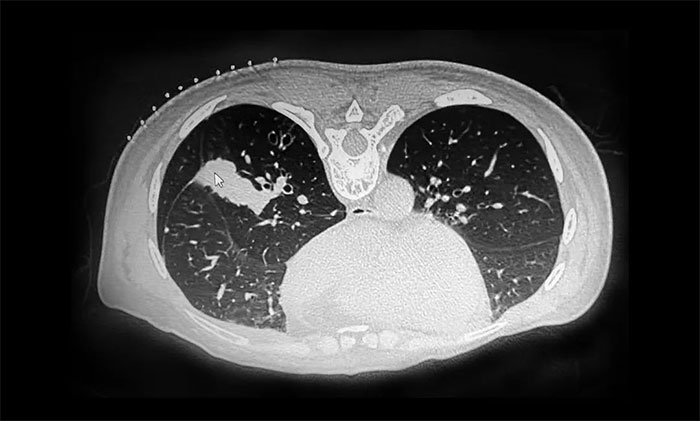

近日,張澤明主任成功開展一例CT引導下經皮肺穿刺活檢術。53歲女性患者陸某(化名)有乳腺癌病史,近期反復咳嗽、咳痰就醫(yī),行肺部CT檢查提示肺部多發(fā)占位。

▲ CT檢查提示肺部多發(fā)占位

由于患者肺部病變位置靠近外周,氣管鏡下難以取得病變部位標本。經醫(yī)院腫瘤科(放療)、十樓重癥監(jiān)護病房、醫(yī)學影像科開展多學科討論,并經反復評估后,決定行CT引導下經皮肺穿刺活檢,以明確診斷。